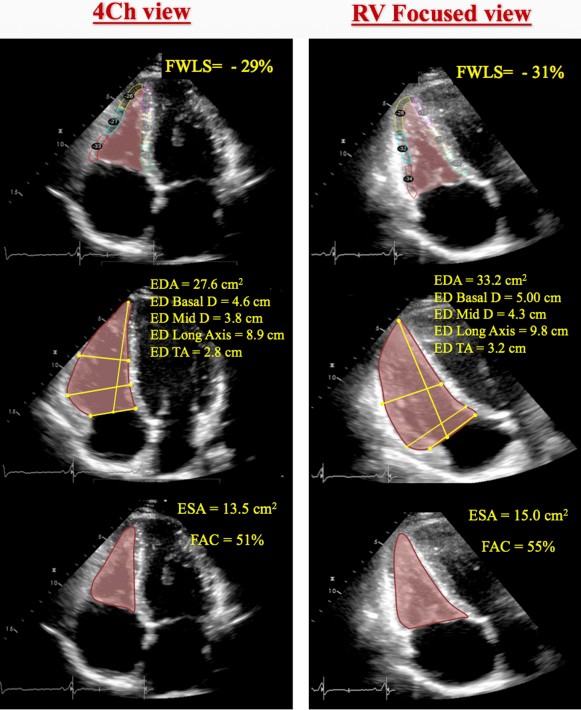

The conventional apical four-chamber view (i.e., focused on the left ventricle) results in considerable variability in how the right heart is sectioned, and consequently, RV linear dimensions and areas may vary widely in the same patient with relatively minor rotations in transducer position (Figure 7B). RV dimensions are best estimated from a RV-focused apical four-chamber view obtained with either lateral or medial transducer orientation (Figure 7A and Table 7). Care should be taken to obtain the image with the LV apex at the center of the scanning sector, while displaying the largest basal RV diameter and thus avoiding foreshortening. Of note, the accuracy of RV measurements may be limited when the RV free wall is not well defined because of the dimension of the ventricle itself or its position behind the sternum. Recent data have suggested that indexing RV “size” to BSA may be relevant in some circumstances, but the measurements used in those studies lacked the reference points of the RV-focused view and frequently used RV areas, rather than linear dimensions. 2

- 🌟RV focused A4C View: LV apex is at the top of the view, but angulated transducer to tip the RV into better view. This view allows you to measure the maximal RV diameter.

- This is the view that you will want to use to take measurements for RV size

Fractional Area Change (Poor Man’s EF)

- Obtain in RV focused A4C view

- Values < 35% are consistent with RV dysfunction

RV Systolic Strain

Longitudinal strain is calculated as the percentage of systolic shortening of the RV free wall from base to apex, while longitudinal strain rate is the rate of this shortening. 2

- Abnormal if values are less negative than -25% (or lower than 25% in absolute value)

- Should be measured in the RV-focused A4C view